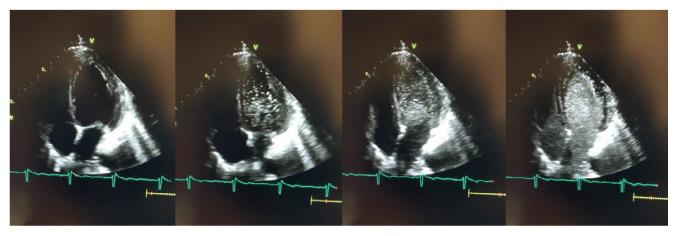

Unusual Cause of Stroke in a Middle-Aged Woman.

https://cdn.ncbi.nlm.nih.gov/pmc/blobs/babf/9110049/0f388cfa9c6f/15-146f1.jpg